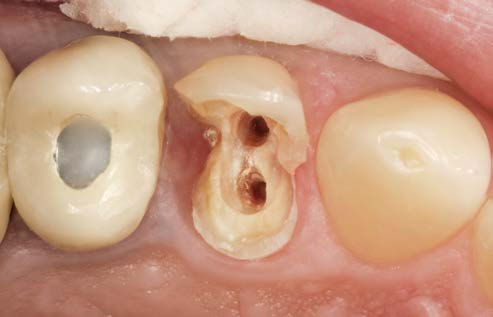

45-річний чоловік звернувся зі скаргою на зуб 24, який

раніше був відновлений за допомогою суцільнокерамічної накладки.

За кілька років після установки накладки знадобилося

ендодонтичне лікування зуба. Тепер було порушено крайове прилягання накладки,

на кераміці видно відколи (рис. 1).

Фото 1. Зуб зі суцільнокерамічною

накладкою.